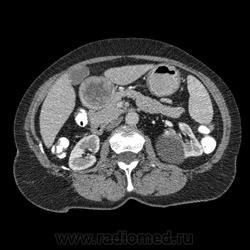

Впечатление, что дуля эта вне головки п.ж., интрамурально в луковице, что ли... тогда возможно GIST, но надо дайком. Утолщение подслизистой в антральном отделе желудка, не удается проследить переход от желудка к 12-перстной((. Внутрипросветно/внутристеночно - не разобрать. 1 фаза?

Клинику! Есть ли признаки высокой тонкокишечной непроходимости, что при ФЭГДС в 12-перстной - туда удалось пройти или нет? ААА! Одни вопросы))))

В-общем, варианты такие без дайкомов: пролапс слизистой в 12перстную, безоар, внутрипросветный дивертикул, гастроинтерстинальная опухоль. И большие сомнения, что это в головке п.ж. - оно отделено от неё тонким слоем жировой клетчатки

Фаз было 3. Видео не выставлял прошлый раз пришел ответ из сайта что видео не работает на сайте Идет накопление контраста в нативе в центре +2+4 по периферии +32+34 .в артериальную +20 и +65 +70 соответственно.

Что оно копит - бог с ним... если это пролапс слизистой, то суммация стенок. Безоар бы не копил. Напрягает отек слизистой в антрале... Это должно быть скорее внутри просвета кишки, т.к. оттесняет газ в 12-перстной на периферию. Без дайкомов больше ничем не могу, извините. Подождём мнения коллег.

Как мне видится - пролапс слизистой желудка в 12-перстную. А мнения коллег что-то нетути...

А что растет из левой почки? Может оно же и желудок сдавливает?

Это расширение всей 12- перстной кишки (стаз).